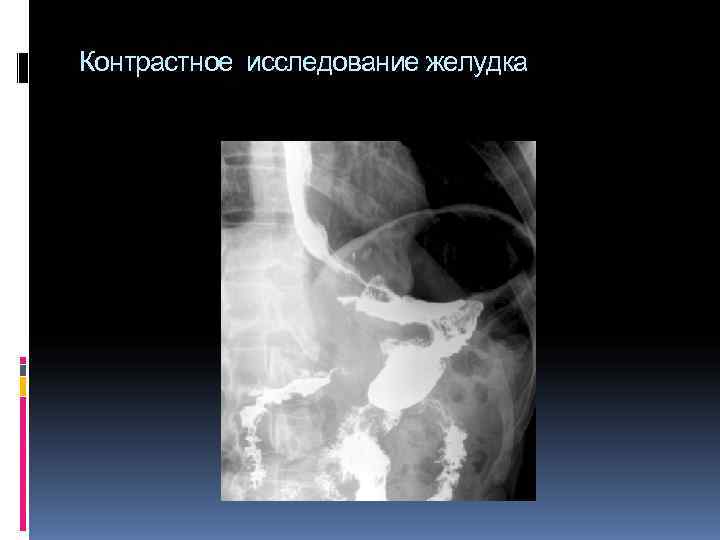

Контрастное исследование желудка

Рентгенологическое исследование желудка Контрастное вещество заполняет межскладочные промежутки, и на экране (снимке) появляется изображение складок слизистой оболочки При этом определяют положение, форму и величину желудка, его тонус, характер тонусов, смещаемость, наличие болевых точек, двигательную функцию (перистальтика, «игра» привратника, ход опорожнения). Далее контрастное вещество переходит в двенадцатиперстную кишку.

Рентгенологическая методика исследования желудка Порция контрастной массы, поступившая в желудок, постепенно опускается из кардиального отдела в тело и антральный отдел желудка, что свидетельствует о нормальном тонусе органа. При повышенном тонусе барий длительно задерживается в верхней части желудка, а при пониженном тонусе сразу падает в дистальный отдел. Складки слизистой оболочки желудка представляют собой подвижные образования